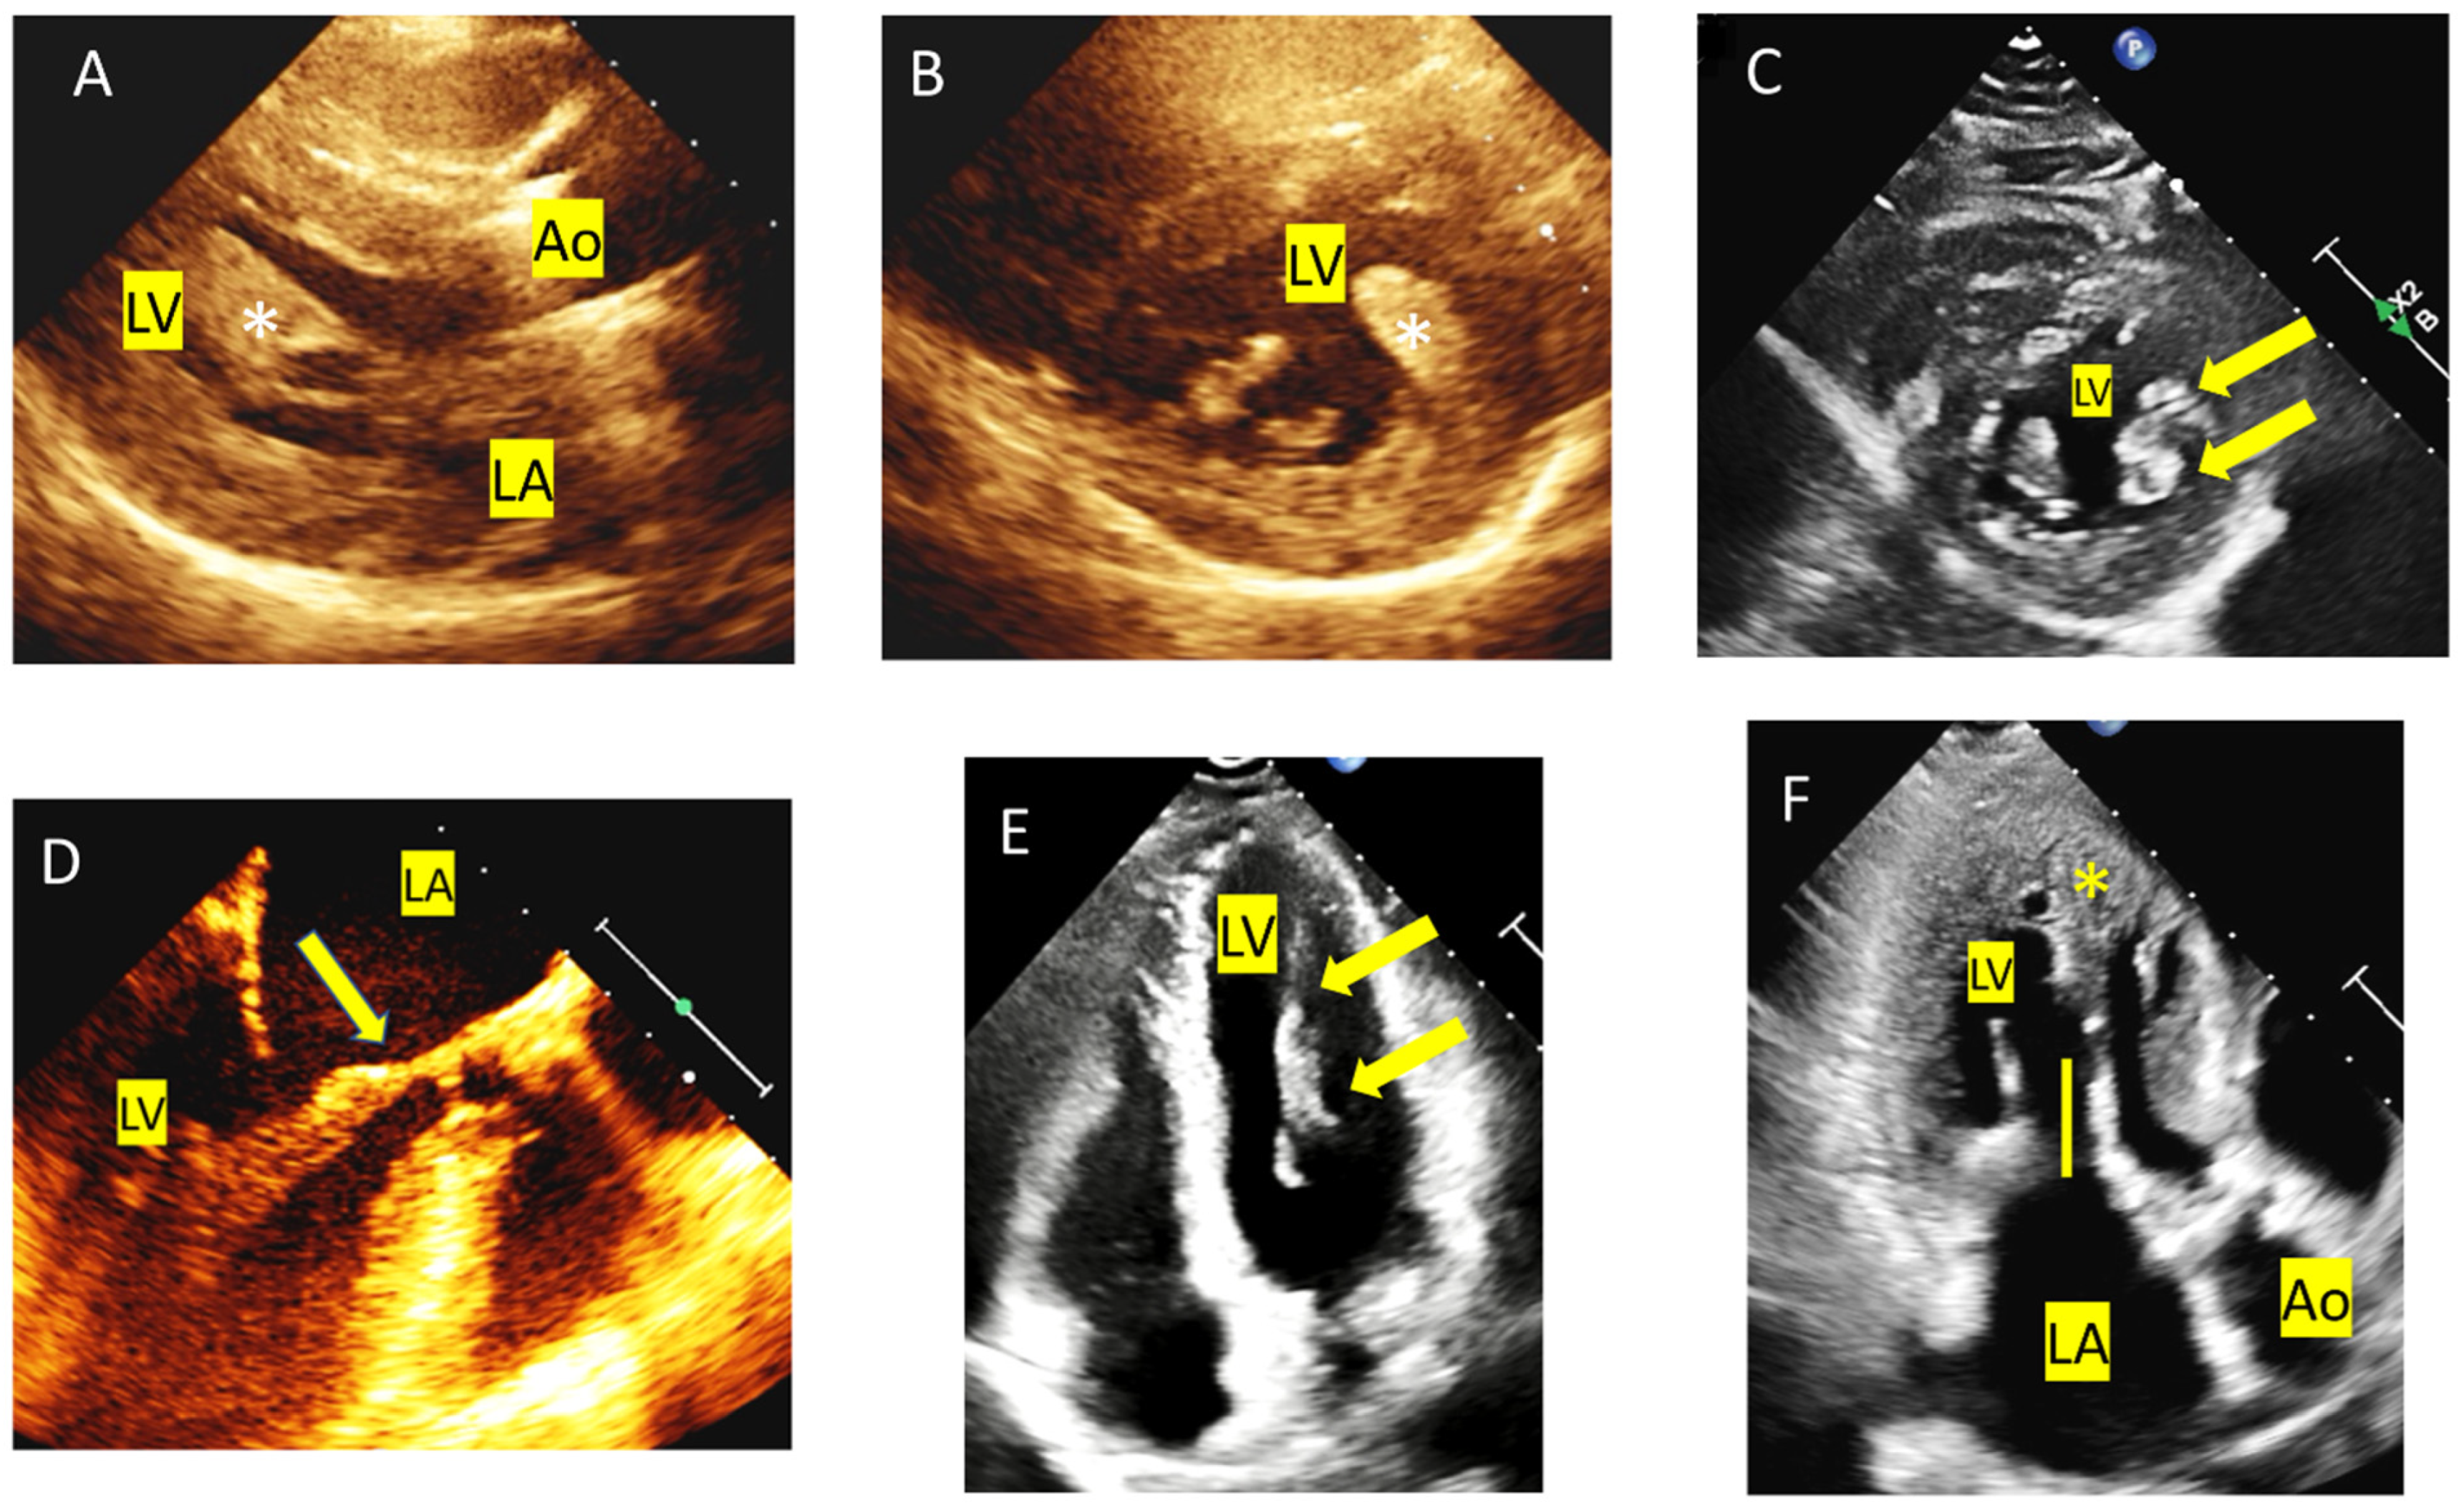

4. Tip and Tricks Concerning LVOT Obstruction Doppler Measurement

5. Mitral Valve Anomalies

- Sherrid, M.V.; Balaram, S.; Kim, B.; Axel, L.; Swistel, D.G. The Mitral Valve in Obstructive Hypertrophic Cardiomyopathy A Test in Context. J. Am. Coll. Cardiol. 2016, 67, 1846–1858. [Google Scholar] [CrossRef]

- Hermida, U.; Stojanovski, D.; Raman, B.; Ariga, R.; Young, A.A.; Carapella, V.; Carr-White, G.; Lukaschuk, E.; Piechnik, S.K.; Kramer, C.M.; et al. Left ventricular anatomy in obstructive hypertrophic cardiomyopathy: Beyond basal septal hypertrophy. Eur. Heart J. Cardiovasc. Imaging 2023, 24, 807–818. [Google Scholar] [CrossRef]

- Captur, G.; Lopes, L.R.; Mohun, T.J.; Patel, V.; Li, C.; Bassett, P.; Finocchiaro, G.; Ferreira, V.M.; Esteban, M.T.; Muthurangu, V.; et al. Prediction of sarcomere mutations in subclinical hypertrophic cardiomyopathy. Circ. Cardiovasc. Imaging 2014, 7, 863–871. [Google Scholar] [CrossRef]

- Petryka, J.; Baksi, A.J.; Prasad, S.K.; Pennell, D.J.; Kilner, P.J. Prevalence of inferobasal myocardial crypts among patients referred for cardiovascular magnetic resonance. Circ. Cardiovasc. Imaging 2014, 7, 259–264. [Google Scholar] [CrossRef] [PubMed]

- Maron, M.S.; Rowin, E.J.; Lin, D.; Appelbaum, E.; Chan, R.H.; Gibson, C.M.; Lesser, J.R.; Lindberg, J.; Haas, T.S.; Udelson, J.E.; et al. Prevalence and clinical profile of myocardial crypts in hypertrophic cardiomyopathy. Circ. Cardiovasc. Imaging 2012, 5, 441–447. [Google Scholar] [CrossRef] [PubMed]

- Spacek, M.; Fiedler, J.; Suchanek, V.; Veselka, J. Echocardiographic detection of myocardial crypts in hypertrophic cardiomyopathy: A first report in phenotype-positive patient. Eur. Heart J. Cardiovasc. Imaging 2014, 15, 1180. [Google Scholar] [CrossRef]